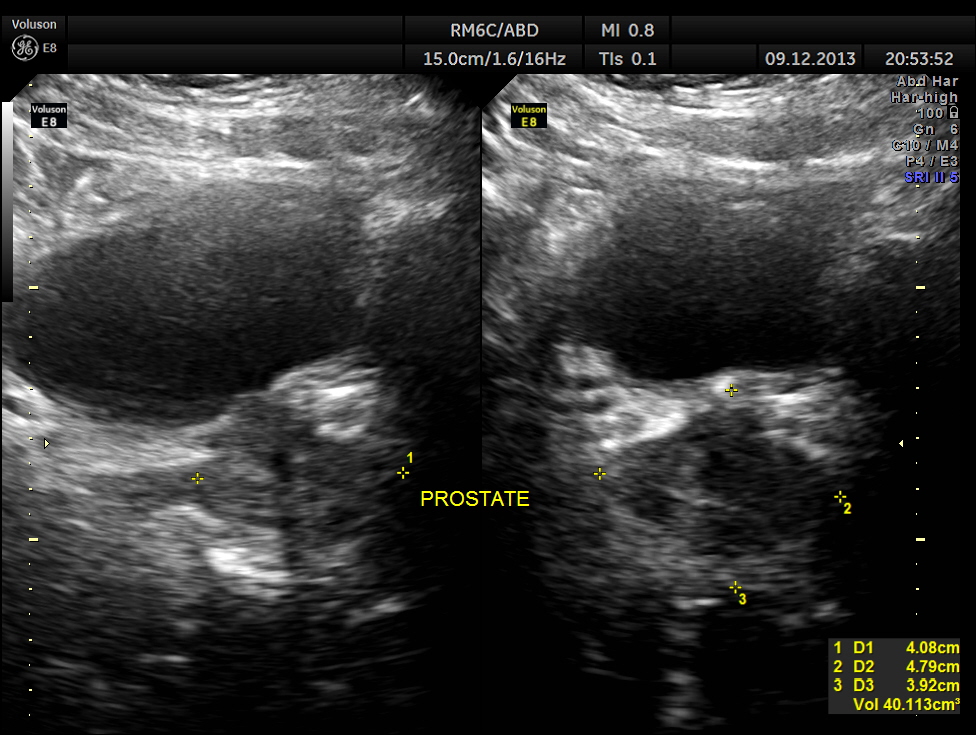

Urinary bladder and prostate are shown below. Mild prostatomegaly seen.

The findings were confirmed with CT Scan . he underwent radical left nephrectomy and the biopsy was reported as RENAL CELL CARCINOMA.